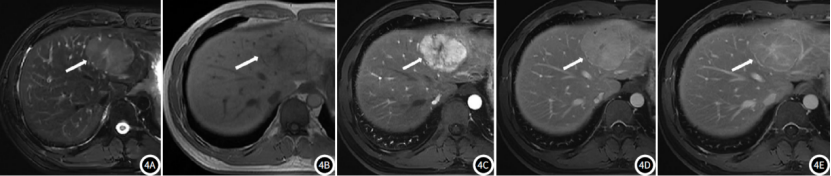

MRI:肝脏体积不大、外缘光整,肝叶比例协调,肝S4见团块状异常信号,T1WI以稍低信号为主,反相位信号无明显衰减,T2WI以稍高信号为主,内见轮辐状T1WI低T2WI高信号(考虑瘢痕),DWI及ADC均呈高信号,SWI病变内无明显低信号,动态增强动脉期肿块呈明显不均匀强化,瘢痕无明显强化,门脉期及过度期持续强化,内部瘢痕渐进强化,肝胆期呈高低不等信号,边界清楚,大小约为31.6mm×28.1mm×32.7mm(左右径×前后径×上下径)。

肝S4占位,考虑局灶性结节性增生(FNH)。

常位于肝包膜下,典型FNH平扫CT呈低密度,中央瘢痕呈更低密度,MRI呈T1WI像呈等或稍低信号,T2WI像因场强及脉冲序列不同可呈等-稍低或等-稍高信号,中央瘢痕T1WI呈更低信号,T2WI因含有慢血流的血管、炎症细胞浸润和水肿的原因一般呈高信号,若瘢痕区血管成分含量较少、血栓机化等,T2WI可为低信号,动态增强动脉期FNH呈明显强化的富血供肿块,部分病变周边或中央可见供血血管,门脉期呈等或略高肝实质密度/信号影,延迟期呈等或略低密度/信号,中央瘢痕早期无强化,延迟期强化;普美显增强肝胆期病灶呈等或稍高信号,主要原因如下①FNH中含有正常功能的肝细胞,能够摄取普美显,中央瘢痕呈低信号;②FNH中肝细胞膜上有机阴离子转运肽(OATP)表达量等于或高于周围正常组织;③FNH内异常增生的胆管系统与正常的肝内胆管无交通,对比剂排泄受阻而积聚在病灶内;中央瘢痕肝胆期呈低信号。